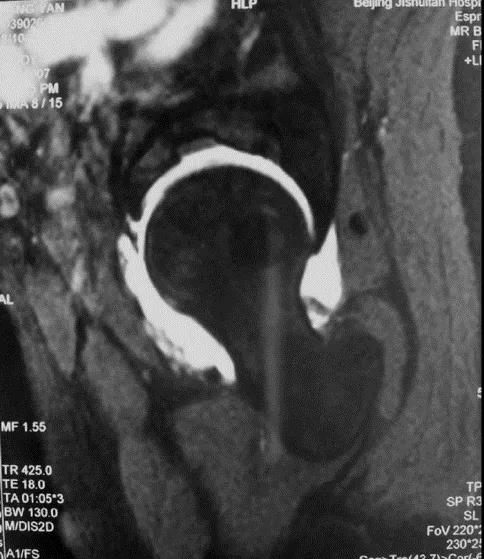

MRI:有不同程度的盂唇撕裂和损伤,对诊断有重要意义

髋臼唇损伤原因:外伤或脱位;退变;先天性髋发育不良;股骨髋臼撞击。发生部位:多在前方和上方盂唇;后唇少见;两处以上撕裂不常见;臼唇与关节软骨交界处诊断方法:MR和MR造影